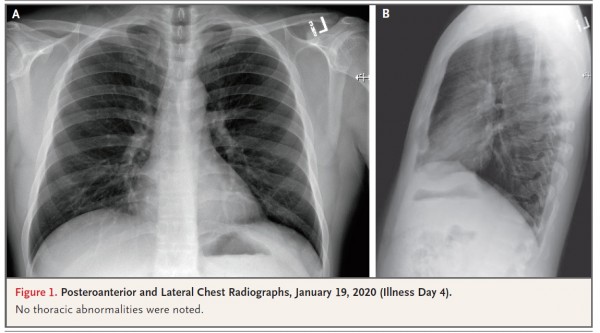

An outbreak of novel coronavirus (2019-nCoV) that began in Wuhan, China, has spread rapidly, with cases now confirmed in multiple countries. We report the first case of 2019-nCoV infection confirmed in the United States and describe the identification,

diagnosis, clinical course, and management of the case, including the patient’s initial mild symptoms at presentation with progression to pneumonia on day 9 of illness. This case highlights the importance of close coordination between clinicians and public health authorities at the local, state, and federal levels, as well as the need for rapid dissemination of clinical information related to the care of patients with this emerging infection.